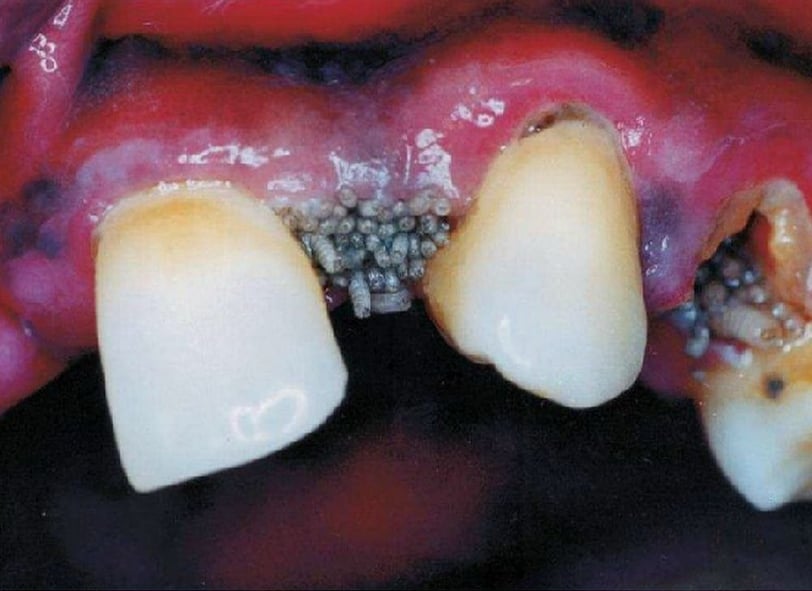

A miíase oral é definida como a infestação de larvas de moscas em cavidades orais ou no tecido intraoral. Essa condição ocorre principalmente em regiões tropicais e subtropicais, onde determinadas espécies de moscas são abundantes. O termo "miíase" origina-se do grego "myia", que significa "mosca", e descreve essencialmente a interação entre os insetos e os tecidos vivos. Os tipos mais comuns de moscas que podem levar à miíase oral incluem a Lucilia sericata e a Musca domestica, que são atraídas por bactérias presentes em feridas ou restos orgânicos, criando um ambiente propício para a ovoposição.

Reconhecer os sinais da miíase oral é fundamental, pois a infestação pode causar sérios danos à saúde bucal e geral dos indivíduos. Os sintomas frequentemente incluem dor intensa, inflamação, e a presença visível de larvas, além de mau cheiro oriundo da infecção. Em casos avançados, pode haver comprometimento do tecido que, se não tratado, pode levar a complicações sistêmicas mais severas. A condição não afeta apenas a cavidade oral, mas pode também ter repercussões na qualidade de vida do paciente, limitando a alimentação e a interação social.

A miíase oral é uma condição caracterizada pela infecção causada por larvas de moscas que se desenvolvem em tecidos bucais. Os sintomas clínicos dessa condição podem variar em intensidade e podem se manifestar através de sinais visíveis e sintomas sistêmicos. Uma das características mais evidentes da miíase oral é o inchaço na região afetada. Este inchaço pode ocorrer nas gengivas, língua ou outras partes da boca, resultando em desconforto significativo para o paciente.